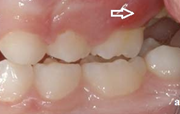

Esimeste molaaride (purihammaste) lõikumine. 1. molaaride ektoopilise lõikumise jälgimine. Ülemised ja alumised esimesed purihambad e. molaarid lõikuvad orienteeruvalt6-7-aastaselt piimahammaste rea lõppu. Enamasti lõikuvad samanimelised jäävhambad paaridena. Normaalne lõikumise Loe edasi »

- valehambumus (18)